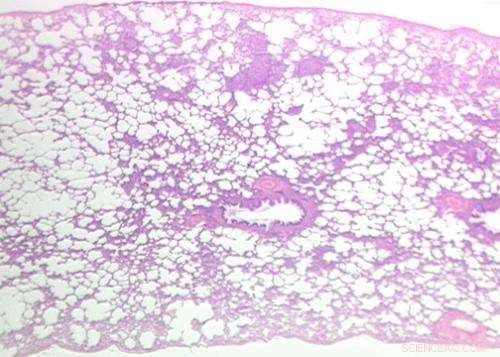

Lung tissue. Credit: Rutgers University